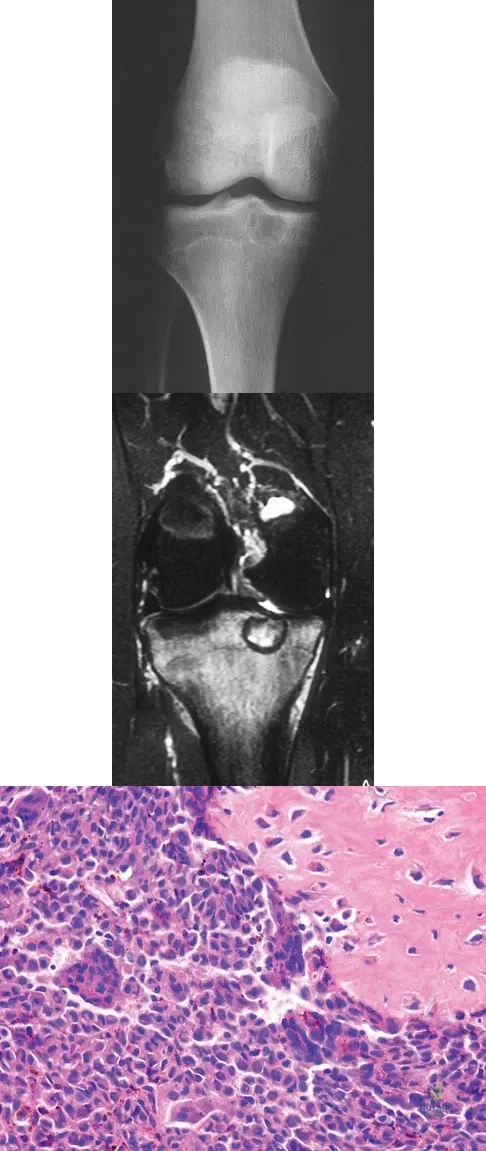

Question 16

A 15-year-old girl reports a 6-month history of activity-related knee pain and swelling. A radiograph, MRI scan, and biopsy specimen are shown in Figures 21a through 21c. What is the most likely diagnosis?

Explanation